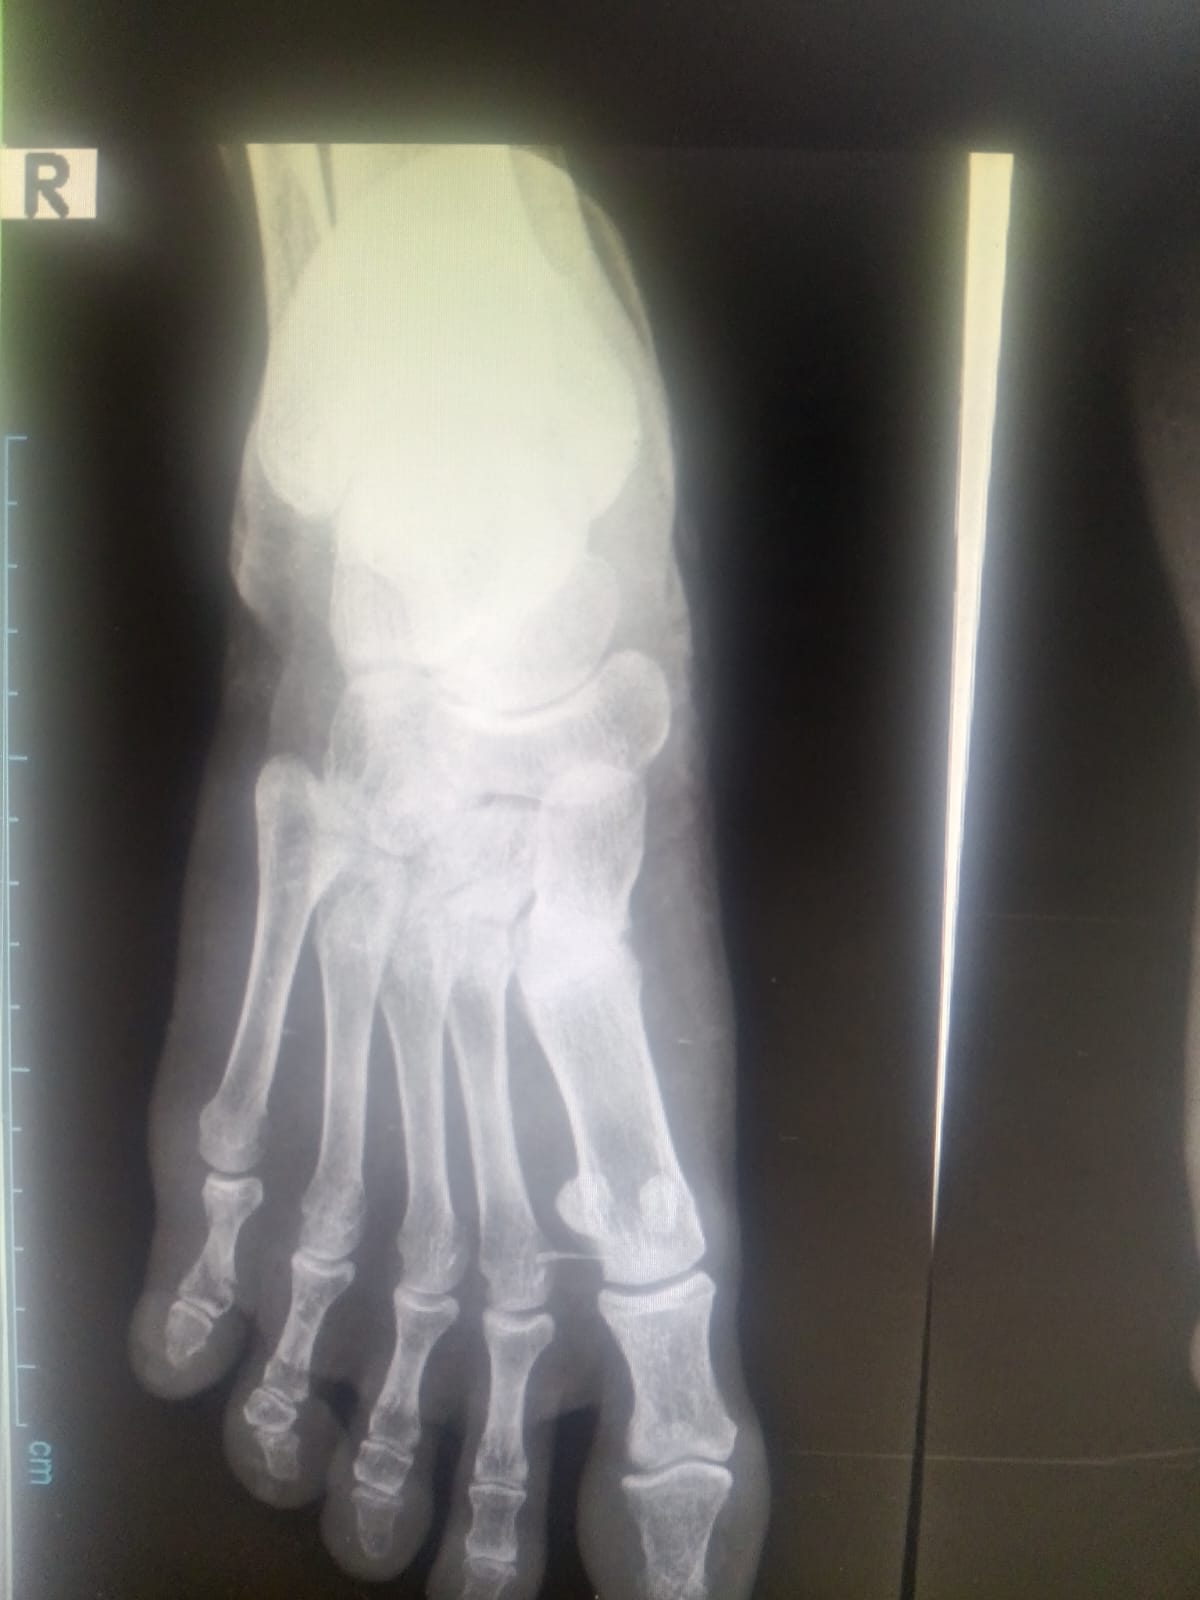

दैनिक आपली मातृभूमीचे पत्रकार सचिन इंगळे यांना पायाला दुखापत झाल्यानंतर त्यांनी १७ एप्रिल २०२६ रोजी अंजनगाव सुर्जी येथील ग्रामीण रुग्णालयात वैद्यकीय तपासणी करून घेतली. तेथे उपस्थित वैद्यकीय अधिकाऱ्यांनी त्यांच्या दुखापतीचे स्वरूप लक्षात घेता एक्स-रे काढण्याचा सल्ला दिला. त्यानुसार एक्स-रे काढण्यात आला. पुढील दिवशी म्हणजे १८ एप्रिल रोजी एक्स-रे अहवाल मिळाल्यानंतर संबंधित डॉक्टरांनी पायाला फ्रॅक्चर असल्याची शक्यता व्यक्त करत पुढील उपचारासाठी अचलपूर येथील उपजिल्हा रुग्णालयात जाण्याचे निर्देश दिले.

निर्देशानुसार सचिन इंगळे दुपारी सुमारे १२.३० वाजताच्या सुमारास अचलपूर उपजिल्हा रुग्णालयात पोहोचले. तेथे नियमित प्रक्रिया पूर्ण करून त्यांना एका वार्डमध्ये पाठवण्यात आले. प्राथमिक तपासणीदरम्यान संबंधित डॉक्टरांनी अहवालाची ओझरती पाहणी करून त्यांना दुसऱ्या वार्डमध्ये जाण्यास सांगितले. यानंतर घडलेली घटना मात्र आरोग्य व्यवस्थेतील दुर्लक्षाचे जिवंत उदाहरण म्हणून समोर येत आहे.

सदर वार्डमध्ये उपस्थित कर्मचाऱ्यांकडून अपेक्षित वैद्यकीय उपचार न देता केवळ साधी पट्टी बांधण्यात आली. फ्रॅक्चरचा संशय असताना प्लॅस्टर न करता रुग्णाला परत पाठविणे हे वैद्यकीय दृष्टीने गंभीर बाब मानली जाते. याच दरम्यान, उपचार करणाऱ्या कर्मचाऱ्याने स्वतःला प्लॅस्टरविषयी अनुभव नसल्याचे सांगितल्याची माहिती पुढे येत आहे. या विधानामुळे रुग्णालयातील प्रशिक्षित मनुष्यबळाच्या उपलब्धतेवर मोठा प्रश्नचिन्ह निर्माण झाला आहे.